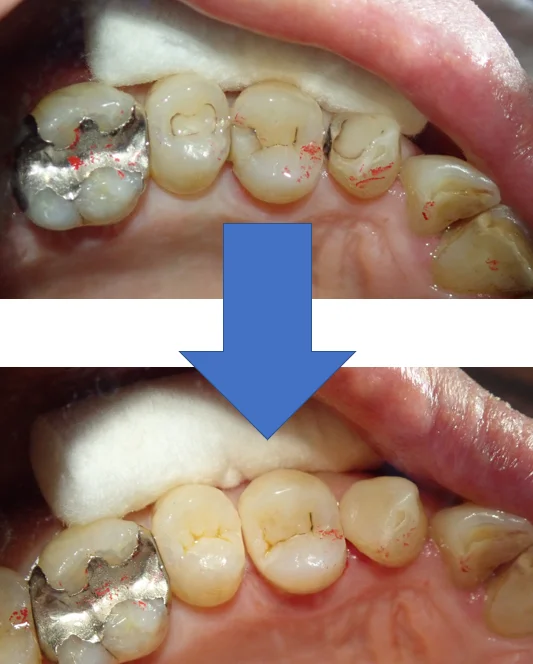

さて、症例の写真に戻ります。

虫歯を取りきった術中写真がこちらです。

案の定、結構な部分が虫歯で、歯がありませんでした。

・・・が、 中心部分・かみ合わせ的にダイレクトボンディングでも十分に持たせることが出来ると判断し、予定通りダイレクトボンディングの修復に入りました。

そして、術後です。

まずは咬合面観で、

次が、頬側面観です。

この治療を行ったとき、裂溝(歯の溝)の再現用のステイン剤で黒を持っていなかったので、真ん中の歯のシェードの再現が微妙になってしまいましたね・・・。

なるべく色はごまかしてみましたが・・・。

治療の精度としては問題はなく、フロスもまったく引っかからないように出来たので、安心です。

後はこれがどれだけ持つかですね!